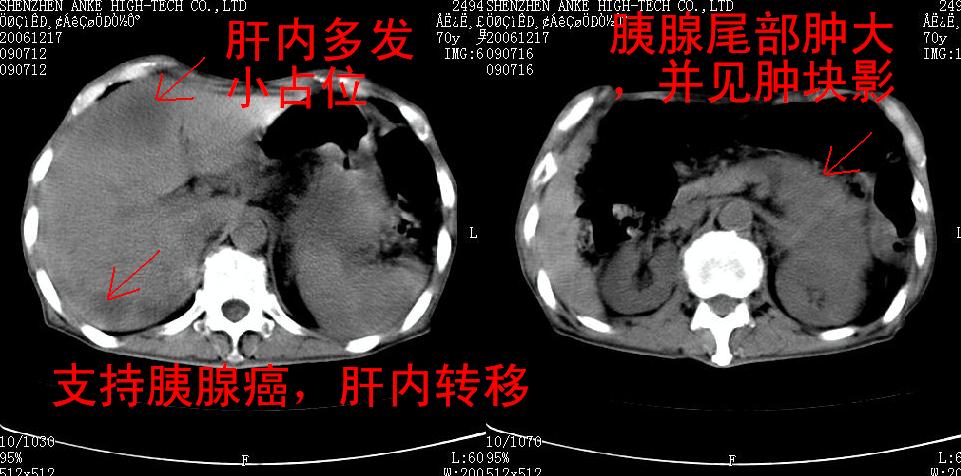

患者:男,70岁,腹部疼痛待查.b超见左肾脏占位待排.因为患者经济条件不好,没有做增强.

支持胰腺癌伴肝转移;左肾囊肿?

胰尾与左肾上缘部位见有一肿块影,密度不均匀,周围边界不清晰,与胰腺相连,与左肾边界不清,肝脏内见有多发低密度影,考虑胰尾癌伴左肾侵犯并肝内转移。最好是做个增强。

考虑:1,胰腺癌伴肝转移;2,左肾小囊肿。

与胃、脾及左肾之间见一巨大肿块影,其内密度不均,边界欠清,与胰腺关系密切。肝实质内见多个类圆形低密度灶,边界较清。符合胰腺癌并肝转移表现。

考虑:1,胰腺癌伴肝转移;2,左肾小囊肿. 3胰腺病变与左肾分界不清,肾脏可能受累。

与胃、脾及左肾之间见一巨大肿块影,其内密度不均,边界欠清,与胰腺关系密切。肝实质内见多个类圆形低密度灶,边界较清。符合胰腺癌并肝转移表现。

同意胰尾部癌累及左肾前,肝多发转移,左肾小囊肿。

胰尾与左肾上缘部位见有一肿块影,密度不均匀,周围边界不清晰,与胰腺相连,与左肾边界不清,肝脏内见有多发低密度影,考虑胰尾癌伴左肾侵犯并肝内转移。最好是做个增强。